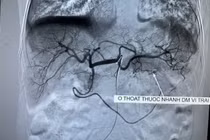

Với phương pháp nút mạch cầm máu cấp cứu, các bác sĩ Bệnh viện Đa khoa tỉnh Lạng Sơn đã cấp cứu thành công bệnh nhân 66 tuổi chảy máu từ dạ dày.

Ổ chảy máu trên màn hình - Ảnh BVCC